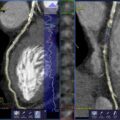

- Автоматическая сегментация коронарных окклюзий, определение и цветовое кодирование центральных линий.

- Цветовая кодировка указывает ракурс сегмента сосуда. Это позволяет выбрать оптимальный угол сегмента поражения, который обычно не виден на рентгенограмме до фактического начала процедуры.

- Кодированные цветом центральные линии используются для регистрации во время процедуры. Таким образом, требуется меньше ангиографических изображений.

При интервенционном вмешательстве CTO syngo CTO Guidance упрощает процедуры позиционирования проводника, обеспечивая параллельный (рентгеноскопические и КТА изображения) контроль. Дополнительная информация, такая как данные о кальцификации и истинная длина областей тромбированных сосудов, помогает правильно выбрать проводник, ориентацию и успешно провести операцию.